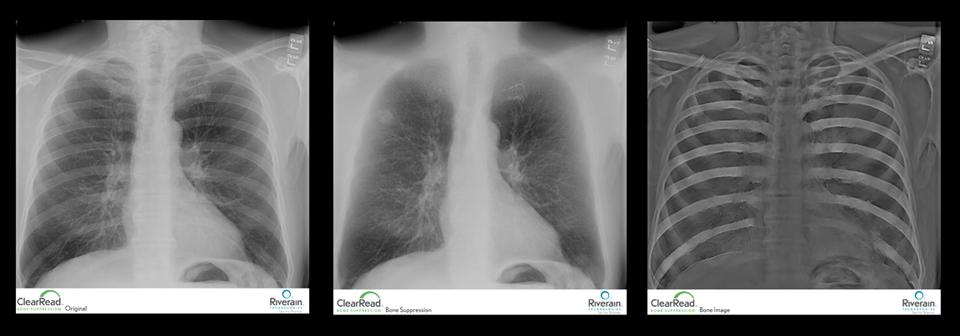

ClearRead Bone Suppression forms a soft tissue image by subtracting the ribs and clavicles from the standard chest X-ray, allowing radiologists to more effectively detect lung disease. Powered by cutting-edge machine learning, it is the only software product to perform robust, pixel level bone suppression throughout the entire body, according to Riverain.